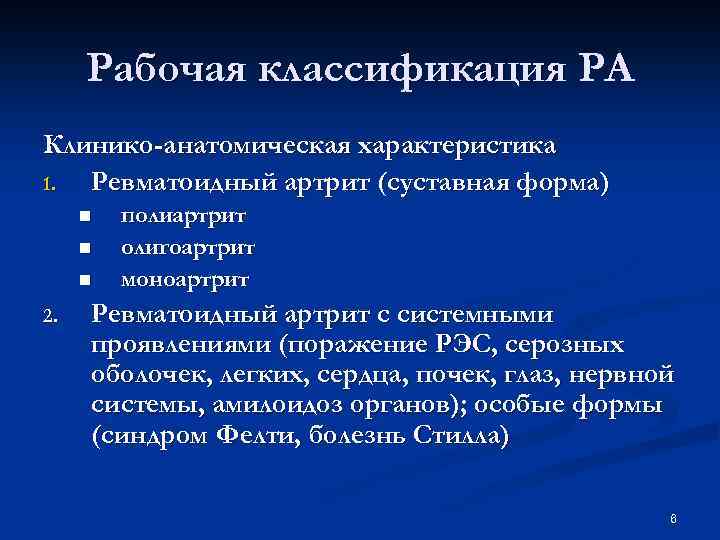

Рабочая классификация РА Клинико-анатомическая характеристика 1. Ревматоидный артрит (суставная форма) n n n 2. полиартрит олигоартрит моноартрит Ревматоидный артрит с системными проявлениями (поражение РЭС, серозных оболочек, легких, сердца, почек, глаз, нервной системы, амилоидоз органов); особые формы (синдром Фелти, болезнь Стилла) 6

Рабочая классификация РА Клинико-анатомическая характеристика 1. Ревматоидный артрит (суставная форма) n n n 2. полиартрит олигоартрит моноартрит Ревматоидный артрит с системными проявлениями (поражение РЭС, серозных оболочек, легких, сердца, почек, глаз, нервной системы, амилоидоз органов); особые формы (синдром Фелти, болезнь Стилла) 6